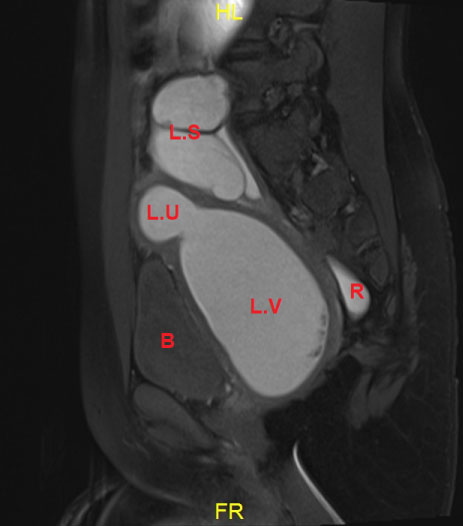

Pelvic MRI showed uterus Didelphis with two hemi-uteri and two hemi-vaginas, the left hemi-vagina was blind, (Figure 1), left hematometro-colpos, and hematosalpinx overlying the dome of the urinary bladder (Figure 2 and Figure 3), Also, it showed left renal agenesis (Figure 4).

Figure 3: MRI image sagital view.

Showing the hemato metro-colpo-salpinx.

B: Bladder; R: Rectum. View Figure 3